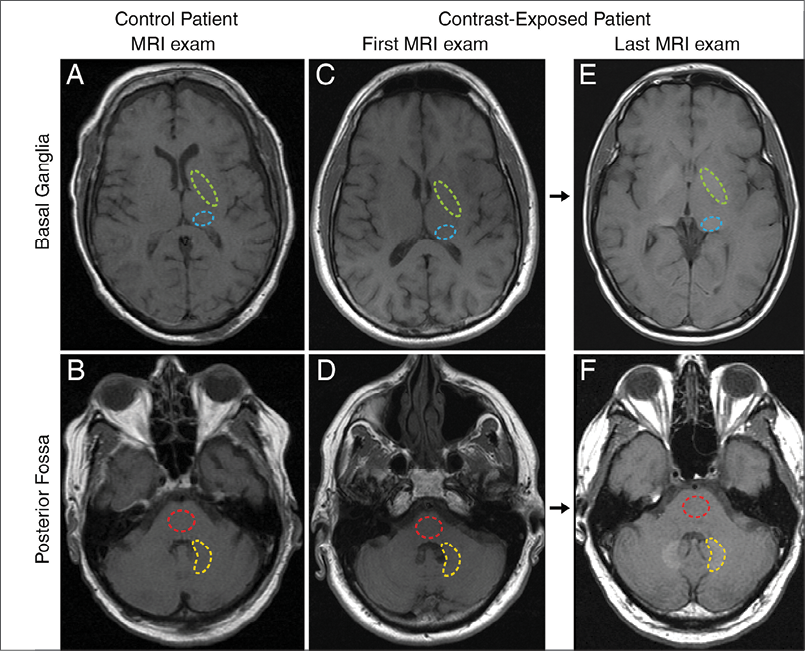

In recent years, new research of MRI studies of patients with a history of multiple GBCA administrations detected hyperintensity indicative of gadolinium in two brain regions: the dentate nucleus and the globus pallidus. The research team led by Tomonori Kanda, M.D., Ph.D., of the Teikyo University School of Medicine in Tokyo, followed up their initial findings with research published in the June 2015 issue of Radiology.

Alexander Radbruch, M.D., J.D., of the University of Heidelberg Medical Center, Germany, and colleagues used MRI to compare two groups of 50 patients who had undergone at least six MRI examinations with either Magnevist, a linear GBCA, or Dotarem, a macrocyclic agent. The researchers found a signal intensity increase in the dentate nucleus and globus pallidus in the linear group but not in the macrocyclic group.